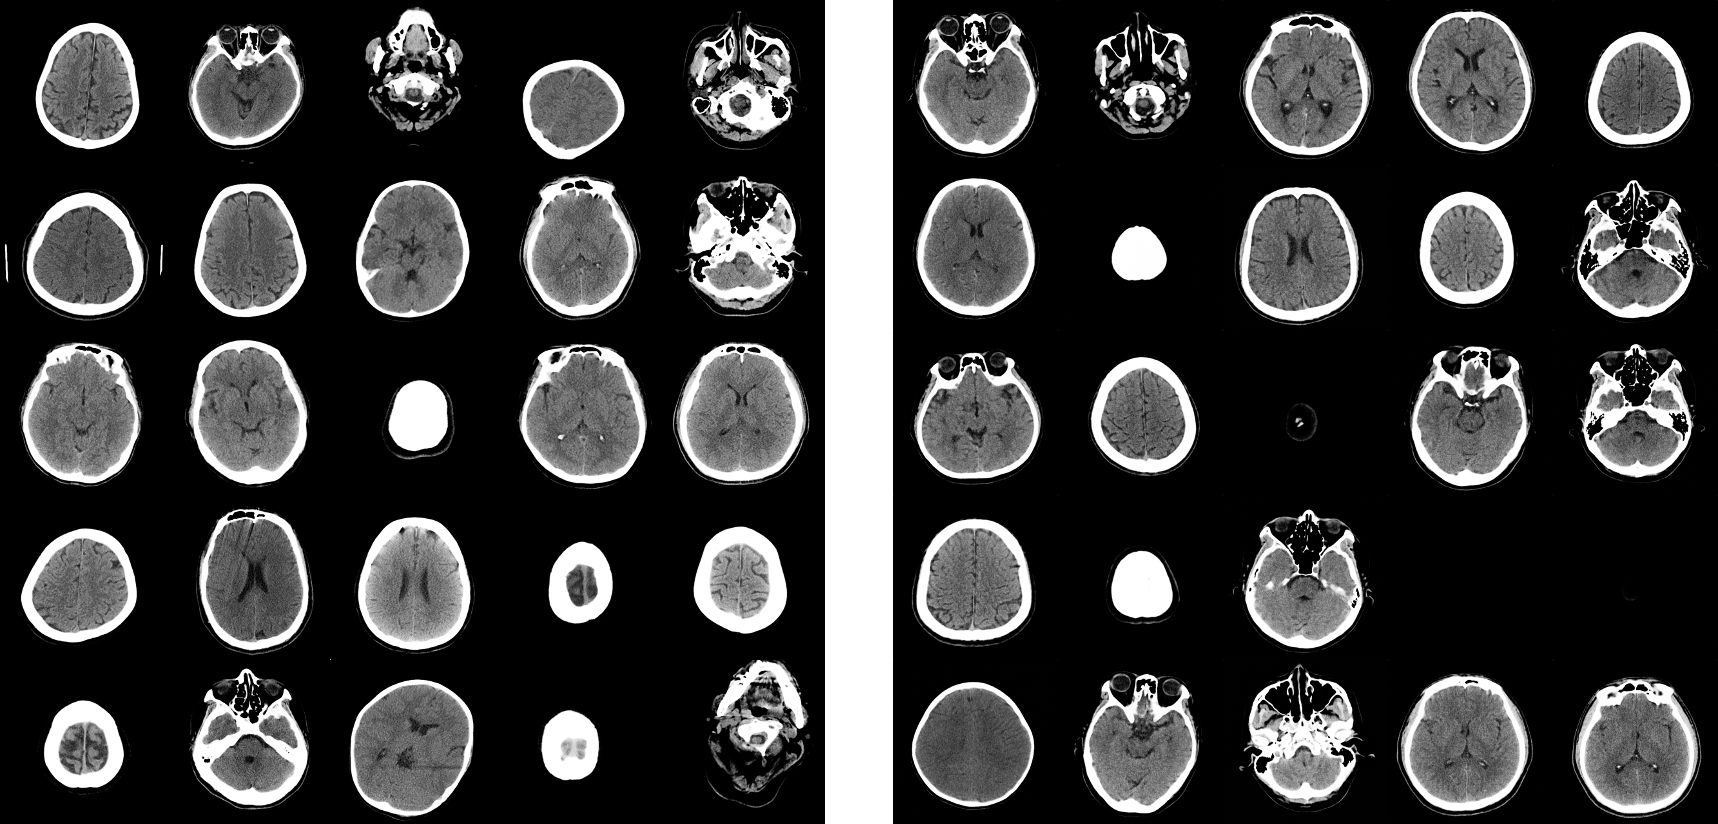

We used StyleGAN2 for brain CT image generation. After the training process, we generated high-quality brain CT images synthetically. A radiologist over 10-years-experience could not notice the difference between real and synthetic images. Examples of sampling of real and synthetic images are shown in Figure (2).

As shown in Figure (2), blank, empty images are also generated, due to the fact that original CT images contain blank, empty images above the head.